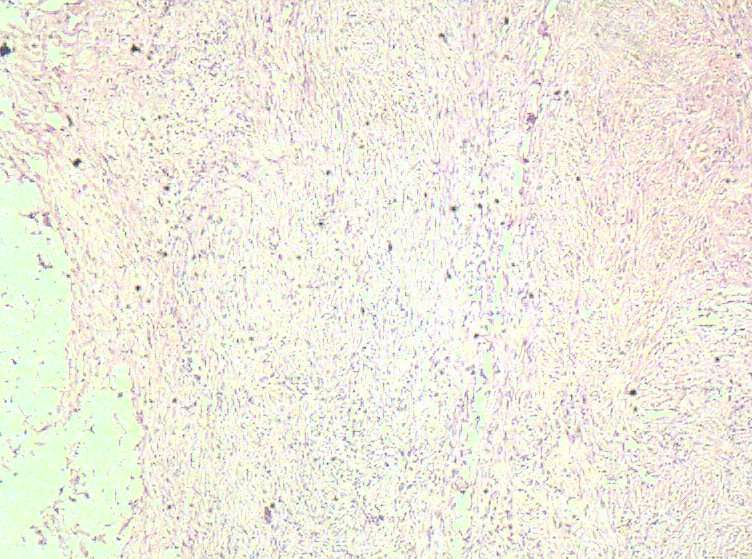

女40岁,发现乳房皮肤表面一年多。

肉眼:不整形组织1.5*1*0.5一侧见皮肤或一侧可见脂肪,切开内一小结节触之稍韧。

• 乳房皮肤表面小结节  请会诊!图1

图1

倾向于皮肤纤维瘤。

皮肤纤维瘤

良性病变。

炎症后的瘢痕结节或者纤维组织瘤样增生?